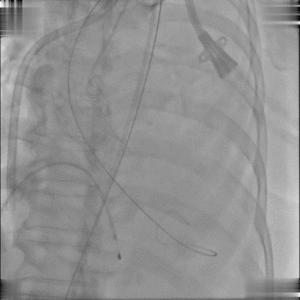

以右侧股动脉为主入路建立双侧入路,Edwards Sapien 3球囊扩张式瓣膜输送系统顺利过弓、跨瓣;随后,行BAV观察患者血流动力学变化情况;

球囊跨瓣

主动脉球囊扩张术(BAV)